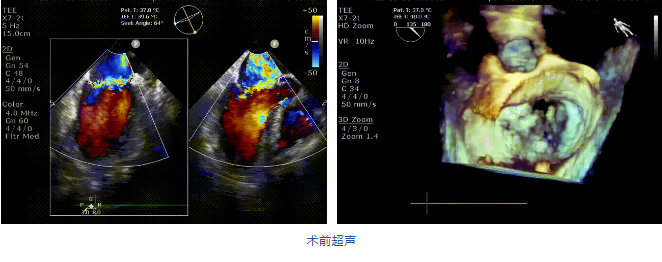

接受治療的是一例二尖瓣重度反流的患者,主訴“突發(fā)間歇性胸悶,氣急6天”。術(shù)前超聲提示:1.二尖瓣脫垂伴重度關(guān)閉不全(瞬時(shí)量30ml);2.左心、右房增大(左房容積110ml,左室容積129ml,右房容積55ml);3.左室收縮功能正常。患者在充分標(biāo)準(zhǔn)化藥物治療后(GDMT)仍然癥狀明顯,韓林教授及其團(tuán)隊(duì)唐楊烽教授,以及心超科的周廣為醫(yī)生決定使用我國(guó)創(chuàng)新器械JensClip為患者進(jìn)行二尖瓣緣對(duì)緣修復(fù)手術(shù)。

在阜外醫(yī)院潘湘斌教授團(tuán)隊(duì)的支持下,手術(shù)經(jīng)股靜脈-房間隔入路,采用全身麻醉插管,在TEE和DSA引導(dǎo)下完成房間隔穿刺。置入JensClip瓣膜夾系統(tǒng)后,在左房調(diào)整瓣膜夾的位置和軸向,后進(jìn)入左室,在TEE引導(dǎo)下捕捉二尖瓣前后瓣葉,并關(guān)閉瓣膜夾。經(jīng)TEE反復(fù)確認(rèn)手術(shù)效果后最終鎖定并釋放瓣膜夾。術(shù)后即刻超聲顯示瓣膜夾位置穩(wěn)定,功能良好,二尖瓣反流由術(shù)前4+減少至微量,手術(shù)圓滿成功。